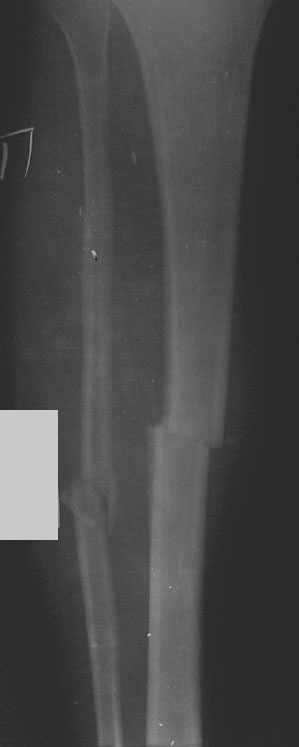

Рентгенограмма голени в прямой проекции

Доставлен машиной скорой помощи больной М. из травмпункта через 1,5 часа после получения травмы, падение с высоты 3-х метров. Бледен АД 105/65 мм рт. ст., пульс 100 в минуту, левая голень фиксирована двумя шинами Крамера.

П

ри

осмотре: после снятия иммобилизации в

средней трети голени отек, резкая

болезненность, нарушение оси конечности.

Имеется воронкообразное втяжение

(умбиликация) кожи над местом перелома,

искривление

оси голени под углом, открытым кнаружи

и кпереди, острый конец верхнего отломка

виден и легко прощупывается под кожей,

определяется ненормальная подвижность

и крепитация костных отломков при

осторожном давлении на место перелома,

местная болезненность при надавливании

на переднюю поверхность и по оси голени.

Деформация голени увеличивается при

поднимании ноги, невозможность опоры

на конечность. При

попытке произвести пассивные и активные

движения, а так же при осевой нагрузке

на голень (поколачивание по пятке

выпрямленной конечности) боль резко

усиливается. Иннервация и кровоснабжение

конечностей не нарушено.